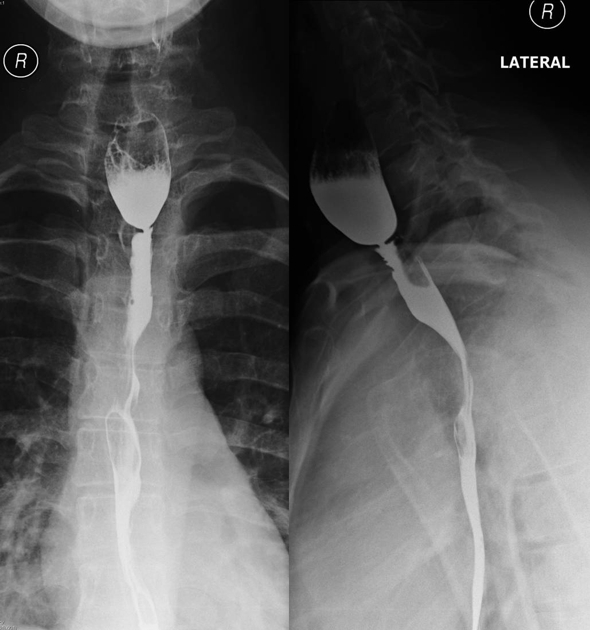

DDx of Dysphagia in Adults

DDx for Dysphagia in Adults

Intrinsic:

Extrinsic:

Neuromuscular: